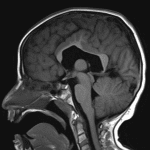

Middle Interhemispheric Variant (MIHV) of Holoprosencephaly

Findings

- Absent septum pellucidum and dysplastic corpus callosum with maintained fibers in the genu and splenium but thinned and dysmorphic appearance of the body and isthmus

- Fusion of the thalami at midline and cross-hemispheric fusion of supracallosal gyri with abnormal cortical thickening

- Colpocephalic ventricular morphology without evidence of hydrocephalus

- Nonspecific mild patchy T2/FLAIR signal hyperintensity in the periventricular white matter

- Abnormal cortical thickening along the posterior aspects of the right greater than left sylvian fissures with polymicrogyria

- Azygos anterior cerebral artery

Diagnosis

- Middle interhemispheric variant (MIHV) of holoprosencephaly

Constellation of findings most consistent with middle interhemispheric variant (MIHV) of holoprosencephaly including: absent septum pellucidum, thinned and dysmorphic appearance of the body and isthmus of the corpus callosum, fusion of the thalami at midline, and cross-hemispheric fusion of supracallosal gyri.

Abnormal cortical thickening and polymicrogyria along the posterior aspects of the right greater than left sylvian fissures as well as abnormal cortical thickening of the bridging supracallosal gyri, all potentially representing possible epileptogenic foci.

Colpocephalic ventricular morphology without evidence of hydrocephalus.

- The middle interhemispheric variant (MIHV) of holoprosencephaly was previously known as syntelencephaly

- MIHV is generally considered to be on the spectrum of holoprosencephaly, though the mechanism is thought to be deficient induction of the neural tube roof plate (dorsal) rather than foot plate (ventral) like classic forms of holoprosencephaly

- A useful distinguishing feature between MIHV and lobar holoprosencephaly is that the body of the corpus callosum is typically most dysplastic in MIHV whereas the genu and rostrum of the corpus callosum are typically most dysplastic in lobar holoprosencephaly

- Imaging findings can include:

- Deficient interhemispheric fissure with failure of separation of the posterior frontal and parietal lobes

- Fusion of the thalami

- Sylvian fissures oriented vertically connecting across the midline over the vertex

- Body of the corpus callosum is usually deficient/dysplastic in the region of interhemispheric nonseparation, whereas the genu and splenium are more normally formed

- Septum pellucidum is usually absent, and the ventricles may show hypoplastic frontal horns

- Cortical dysplasias, heterotopias

- Azygos anterior cerebral artery

- Dorsal interhemispheric cyst